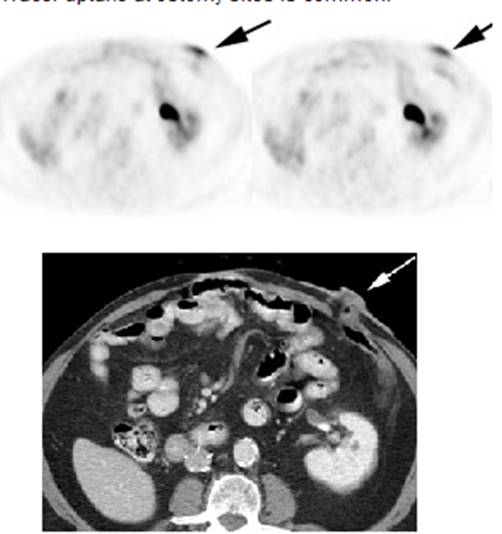

Figure 21 - Marrow activity: The images below are from

two separate patients each showing mild FDG accumulation within the vertebral

bodies.

Figure 22 - Growth colony effect: The patient shown below

had received growth colony stimulating factor (GCSF). Note the extensive

increased marrow activity. Note increased splenic activity also seen as a result of GCSF therapy.